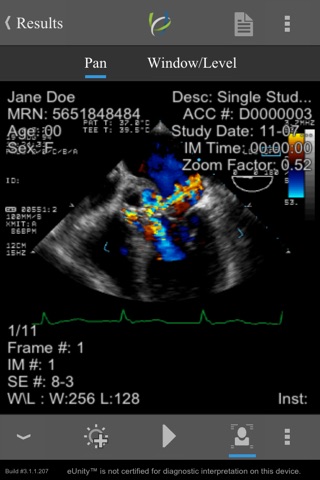

Simple, intuitive, secure - eUnity enables healthcare professionals to access, manipulate and collaborate over full quality medical images. View all image modalities, including X-ray, CT, MRI, color ultrasound and X-Ray angiography. Enhance your workflows by leveraging eUnity in grand rounds, consultations, referrals and reference. Connect to eUnity Server and extend the reach of your medical images to the point of care – wherever it may be.

• Support for all major modalities.

• Phone and tablet support.

• Outstanding, no-compromise performance.